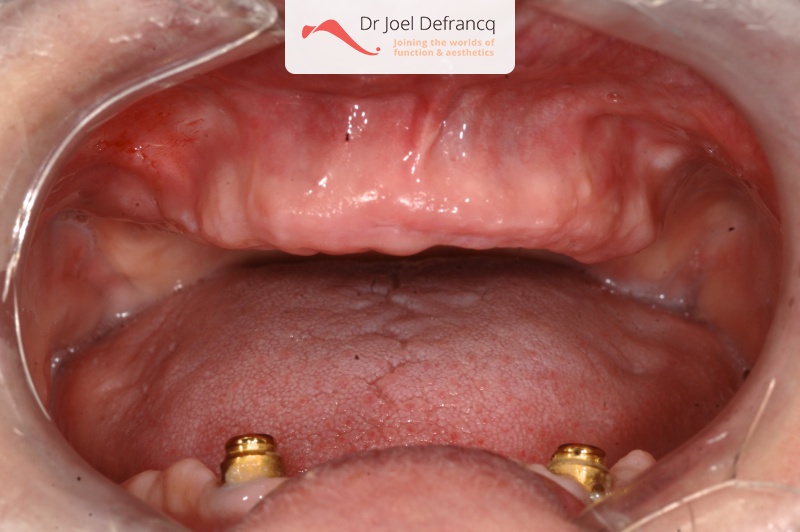

Behandeling tandheelkundige implantaten

- Vaste tanden op implantaten (bovenkaak)

- Vaste tanden op implantaten (onderkaak)

- Implantaten met beenopbouw